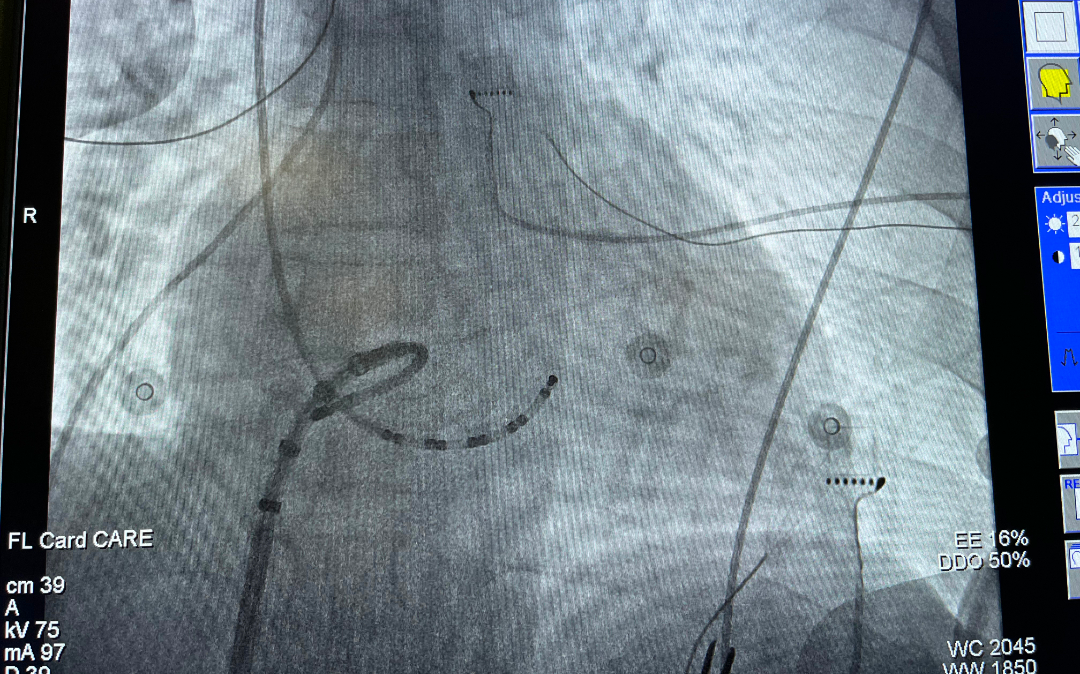

近日,心血管内科桂春主任为新冠阳性室性心动过速(简称「室速」)患者完成手术。47 岁的患者陈某反复发作室速 20 年,近 3 天室速持续性发作,达到心率 190 次/分。此前患者已出现血压下降、头晕眼花等症状,面对这一危急时刻,虽然该患者核酸检测结果为阳性,我院心血管内科随即安排进行射频消融术。手术由桂春教授主刀,手术过程持续 2 个小时,成功找到靶点并消融成功,术后反复诱发均未再诱发出室速。